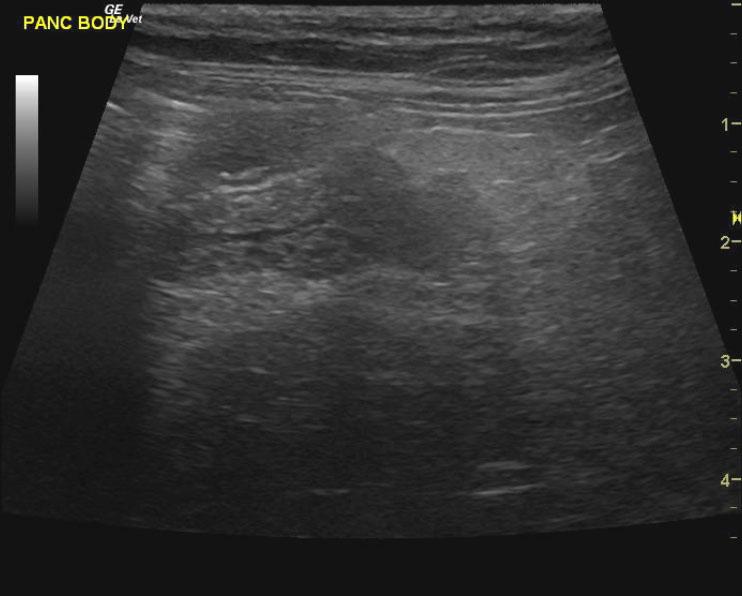

A 15-year-old MN DMH cat was presented for chronic diarrhea, hyperthyroid, dehydration, otitis externa, and periodontal disease. The CBC was markedly normal with blood chemistry revealing an elevated ALT (154,) elevated SAP (109,) hyperT4 (>10,). An IDEXX feline diarrhea panel was negative for virus, parasites, & bacteria.